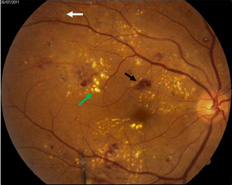

A case of diabetic retinopathy showing hemorrhages (black arrow), hard exudates (yellow spots- green arrow) and neovascular frond- a bunch of abnormal new vessels (white arrow)